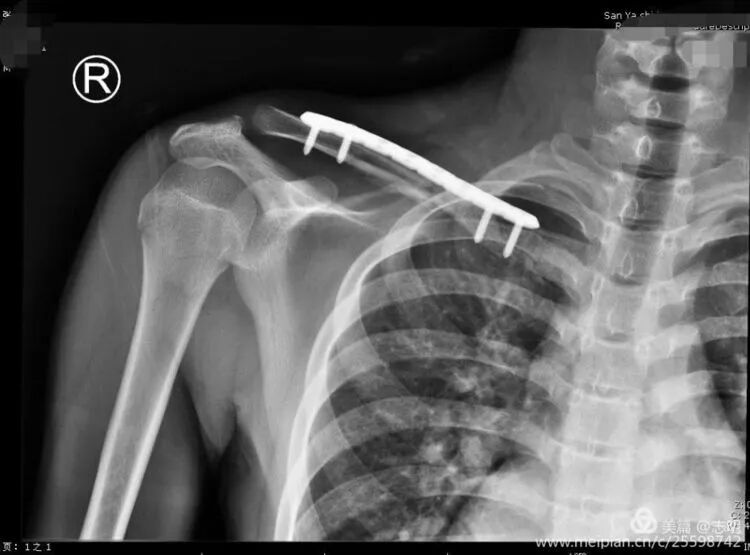

(Fluoroscopy showing K-wire stabilization).

(X-ray showing temporary K-wire fixation after reduction).(Fluoroscopic image demonstrating K-wire placement for temporary reduction).

(Fluoroscopy confirming plate position).(Another fluoroscopy view of plate position).

(Image depicting the insertion of a plate through a small incision).(Fluoroscopic image confirming proper plate positioning).(Another fluoroscopic view illustrating the plate's final position).